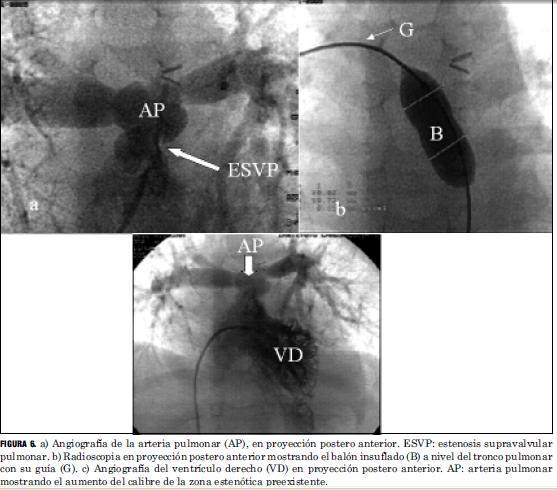

Las lesiones residuales significativas se presentaron en nueve pacientes (15%). Siete pacientes con estenosis supravalvular pulmonar, uno de ellos asociada a estenosis del origen de la arteria pulmonar rama izquierda, que requirieron angioplastia con balón (figuras 6 y 7), siendo efectiva en cuatro, mientras que en los otros tres requirió cirugía reparadora con la colocación de parche de pericardio bovino. Un paciente presentó una comunicación interauricular residual que debió ser cerrada quirúrgicamente, y otro paciente desarrolló una estenosis subaórtica (figura 8) que se resecó quirúrgicamente, todos con buena evolución (tabla 5).

La frecuencia de aparición de lesiones residuales significativas en nuestra serie fue similar a la publicada en la literatura, donde se refiere para la estenosis supravalvular pulmonar una incidencia de 5% a 30%, siendo menor su incidencia con el aumento de la experiencia del equipo. Son factores favorecedores de su aparición la corrección neonatal precoz, la existencia de un banding con larga evolución, la hipoplasia del anillo aórtico y la técnica quirúrgica empleada (16). En los casos de estenosis supravalvular pulmonar hemos tenido un porcentaje de éxito mediante la valvuloplastia con catéter balón, superior al promedio registrado en la literatura. Creemos que ello pueda deberse a múltiples variables a saber: técnica quirúrgica empleada, tamaño de muestra insuficiente para obtener conclusiones estadísticamente significativas. La aparición de una estenosis subaórtica significativa correspondió a un paciente que presentó una leve estenosis subpulmonar previo a la realización del switch arterial, subvalorada en el momento de la realización de dicha técnica.